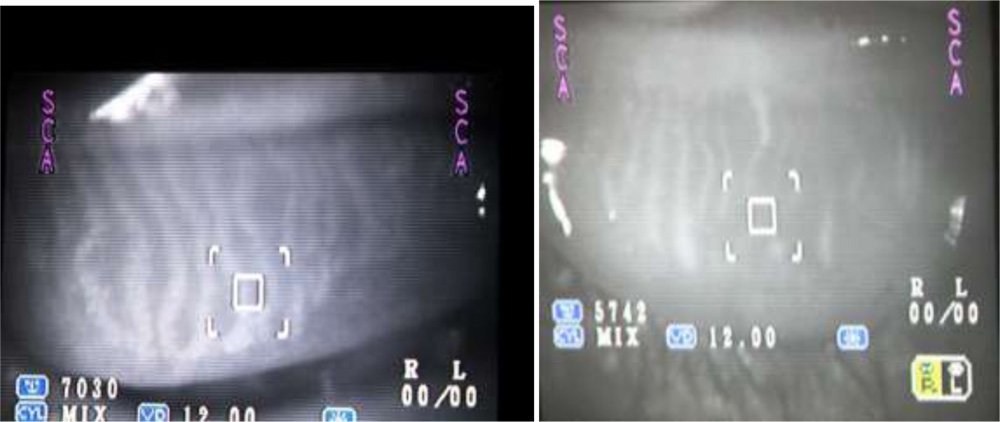

We tried to visualize the MGs by the infra red imaging using autorefractomer (Topcon RM8900), non contact tonometer (CT 80 Topcon), fundus camera (Zeiss), Zeiss  IOL master 500, specular miscroscope ( Topcon SP-3000p), ATLAS 9000 topographer and Visante AS-OCT which we have in our hospital. The images obtained were good enough to visualize the morphological features of MGs in these MGD eyes. We noted gland tortousity, shortening of the glands, broadening of the glands and gland drop-outs to various extent in many eyes. The images obtained by autorefractometer, IOL master, specular microscope, fundus camera, corneal topographer and Visante AS-OCT were better than those obtained by non-contact tonometer (NCT). The central shadowing of NCT while noting the MGs obscures the full visualization of MGs. The sample images obtained from these above mentioned instruments are as follows:

Fundus camera:

Atlas Corneal topographer: